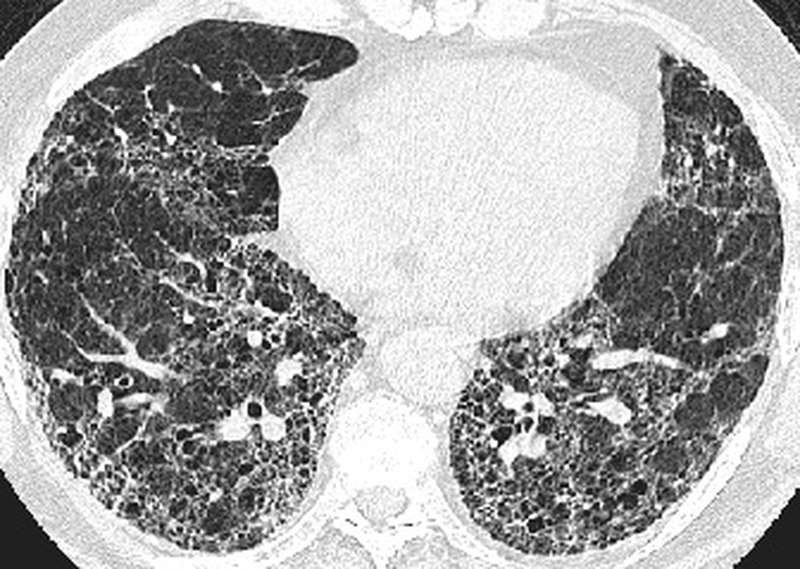

Khi bị xơ hóa phổi sẽ gây ra sẹo trên phổi, khiến phổi bị xơ cứng. Một số triệu chứng của bệnh thường thấy như: Hít thở khó khăn, ho nhiều trong thời gian dài, người thường hay mệt mỏi, sụt cân không rõ nguyên nhân, cảm thấy tức ngực. Bên cạnh đó, còn phụ thuộc vào tình trạng bệnh nhẹ hay nặng sẽ có thêm nhiều nguyên nhân khác nhau đi kèm.

Xơ phổi vô căn là gì? Nguyên nhân, dấu hiệu và cách nhận biết 3 Xơ phổi vô căn ở giai đoạn nặng sẽ gây ra nhiều biến chứng về tim, thận và máu